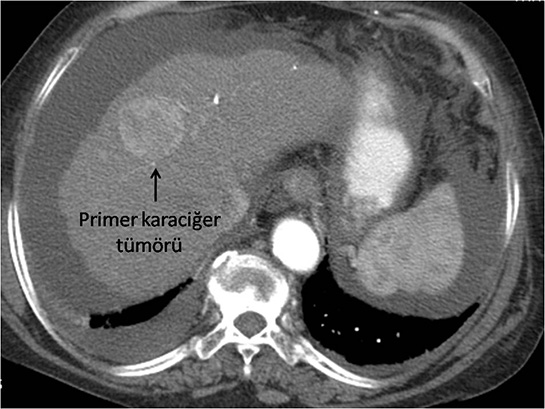

Histopatolojik sınıflama, tümörlerin malignite potansiyelini belirlemede kritik bir rol oynamaktadır. Evrelendirme (Staging) Evrelendirme, tümörün vücutta ne kadar yayıldığını belirlemek için kullanılan bir sistemdir. En yaygın evrelendirme sistemi, TNM sistemidir ve üç ana unsurdan oluşur: